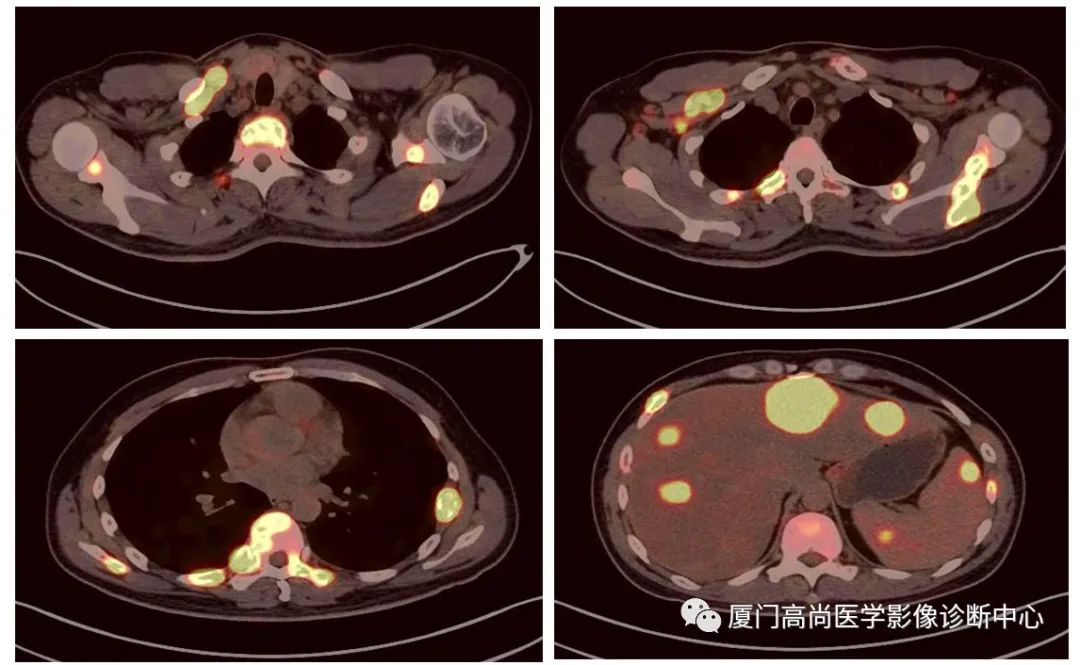

病例2、某女士,62歲,近3個月來自覺消瘦,無其他自覺癥狀,CT發(fā)現(xiàn)雙側(cè)腎上腺增大,性質(zhì)待定,查血各項腫瘤標(biāo)記物均正常,臨床診斷不清,申請做PET/CT檢查

左心房淋巴瘤病灶

右心房淋巴瘤病灶

雙側(cè)腎上腺病灶、膽囊病灶

腹腔淋巴結(jié)腫大

小腸多段淋巴瘤病灶

PET/CT發(fā)現(xiàn) :左心房、右心房見團塊狀FDG攝取增高;雙側(cè)腎上腺增大,F(xiàn)DG攝取增高;膽囊和胃壁結(jié)節(jié)樣FDG攝取增高;小腸多節(jié)段腸壁增厚,F(xiàn)DG攝取增高;腹膜后、腹腔及盆腔多發(fā)淋巴結(jié)腫大,F(xiàn)DG攝取增高;上述考慮為淋巴瘤

經(jīng)腎上腺穿刺活檢 :病理證實為彌漫大B細(xì)胞淋巴瘤